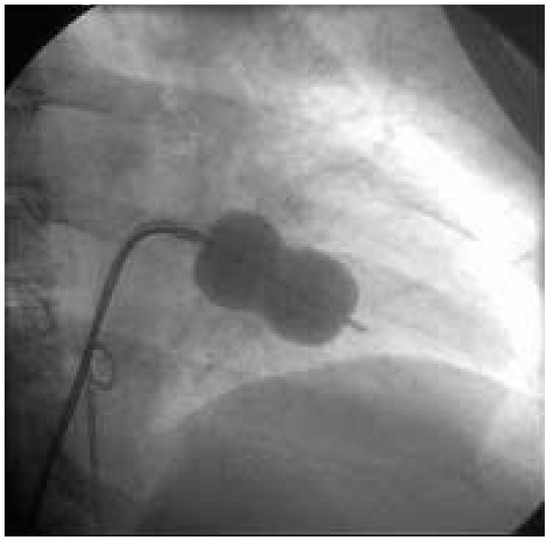

The definition of metabolic syndrome includes the presence of at least three of the following criteria: dyslipidaemia, hyperglycaemia, hypertension, and obesitas. The risk for cardiovascular events is strongly elevated in patients with metabolic synd...